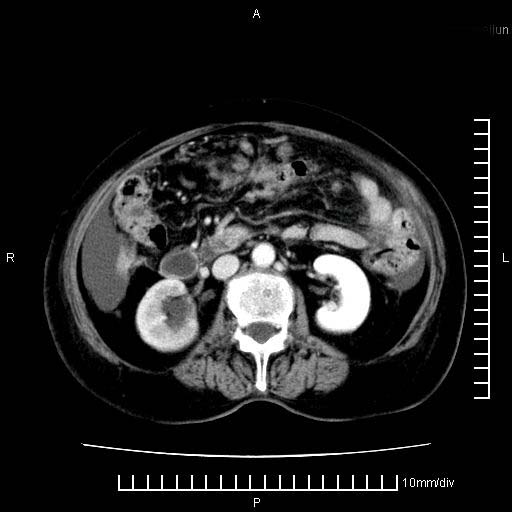

标题: CT28280:腹部增强:女性,80岁

上腹疼痛月余,外院核磁诊断胰腺癌。现临床示右下腹可明显触及包块,可片子上怎么没有看到?

1.胰腺颈体部癌。

4。右肾盂囊肿。

1。胰腺ca伴腹膜腔转移

2。肝左叶低密度灶,考虑转移可能

支持胰腺癌肝内转移,腹水改变。

胰腺结构模糊,胰尾部见囊性包块,周围脂肪密度增高,左肾前筋膜增厚,胸水、腹水。不符合胰腺ca伴腹膜腔转移。考虑胰腺炎伴假性囊肿形成、胸腹腔积液。

1、考虑胰腺癌伴腹膜腔转移,胸腹水。

2、肝脏转移可能。

3、右肾盂囊肿。

1)考虑胰腺癌并胰腺假性囊肿形成。2)肝内低密度灶,不排除转移。3)右肾盂积水。4)腹水。5)右侧胸腔积液并右肺下叶部分膨胀不全。

考虑胰腺ca伴腹膜腔转移、肝左叶转移、右肾积水。右胸腔积液。